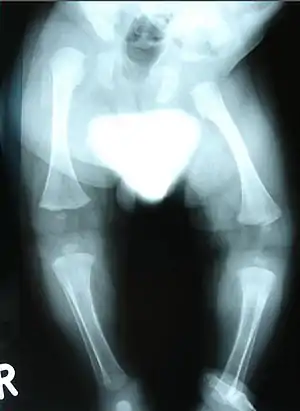

| Radiograph showing dysplasia in lower limbs | |